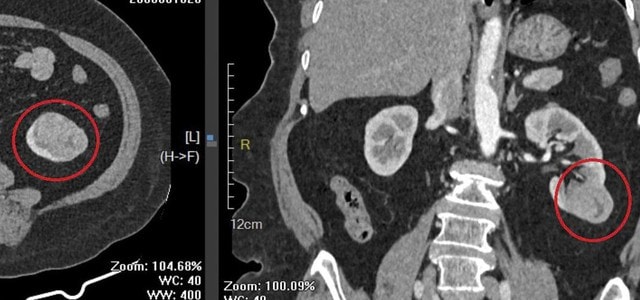

Trong quá trình thăm khám và thực hiện các xét nghiệm cận lâm sàng phục vụ phẫu thuật, các bác sĩ phát hiện khối u tại thận trái.

Sau khi hội chẩn và đánh giá toàn diện tình trạng sức khỏe, ê kíp điều trị thống nhất chỉ định phẫu thuật nội soi cắt một phần thận trái chứa khối u, đồng thời bảo tồn tối đa phần nhu mô thận lành nhằm duy trì chức năng thận cho người bệnh cao tuổi.